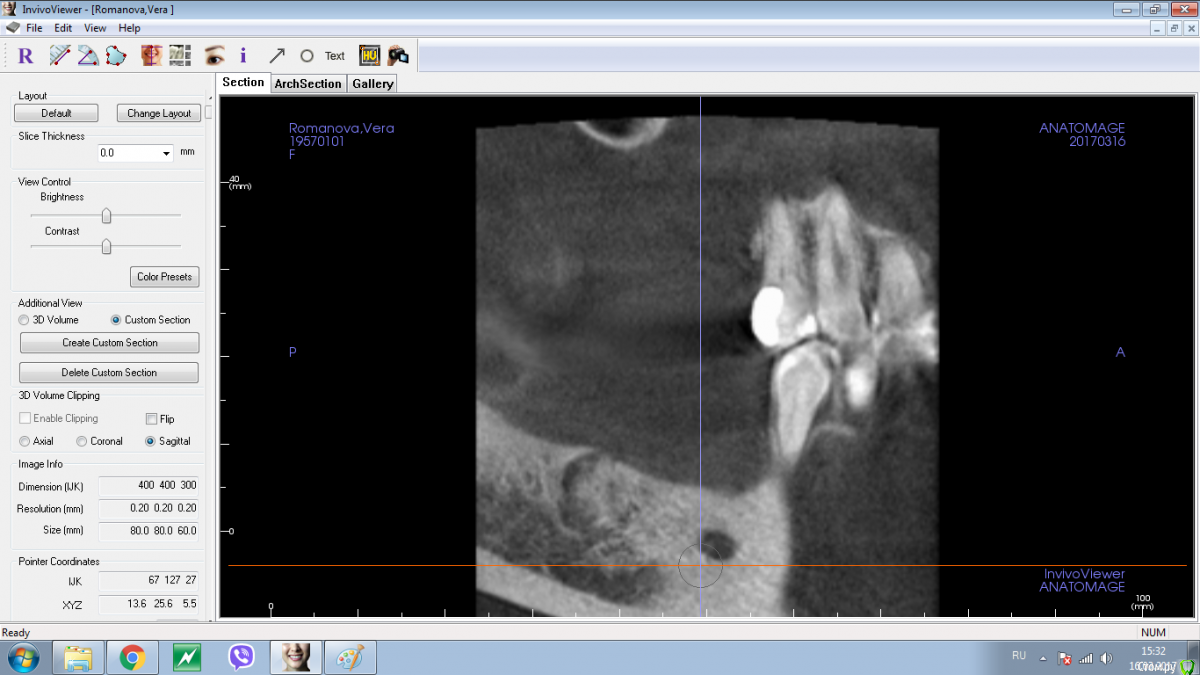

Shakirbura Опубликовано 18 марта, 2017 Поделиться Опубликовано 18 марта, 2017 Здравствуйте, коллеги!Пациентка обратилась по поводу протезирования на имплантатах. На снимке обнаружил вот такое образование. Раньше не встречал. Какими должны быть мои действия в таком случае?Спасибо! Ссылка на комментарий

Andrey Shiryaev Опубликовано 18 марта, 2017 Поделиться Опубликовано 18 марта, 2017 Похоже на остеому. Ссылка на комментарий

Kovalov Igor Опубликовано 19 марта, 2017 Поделиться Опубликовано 19 марта, 2017 Конденсирующая остеома.Покажите на Фейсбуке Рогацкину Дмитрию , читал что ставят прям в остеому Ссылка на комментарий

Карен Аванесов Опубликовано 19 марта, 2017 Поделиться Опубликовано 19 марта, 2017 Аккуратно убрать, поставить имплантат, при необходимости графт, если это остатки зуба будет видно. если нло на гистологию. Ссылка на комментарий